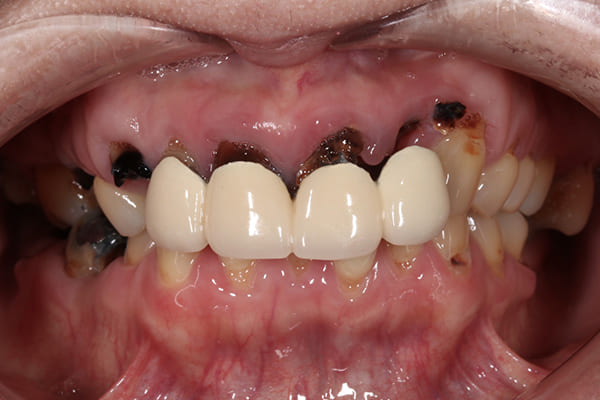

治療前後の比較

このように横に並べると変化がよくわかります。

治療を通じて、患者様の笑顔がより自然で明るくなり、自身を持って笑えるようになったことをとても嬉しく思います。